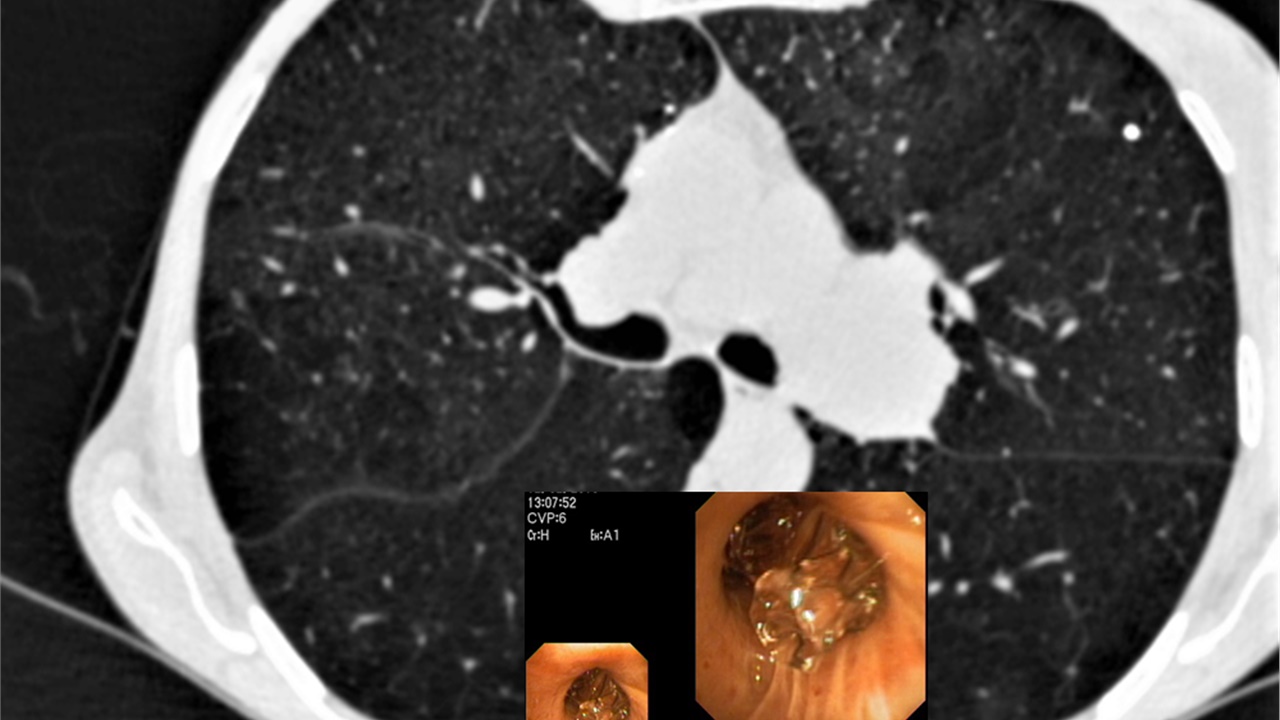

Bronchoscopy On Air #1: Peripheral Pulmonary Lesion / Rebiopsy